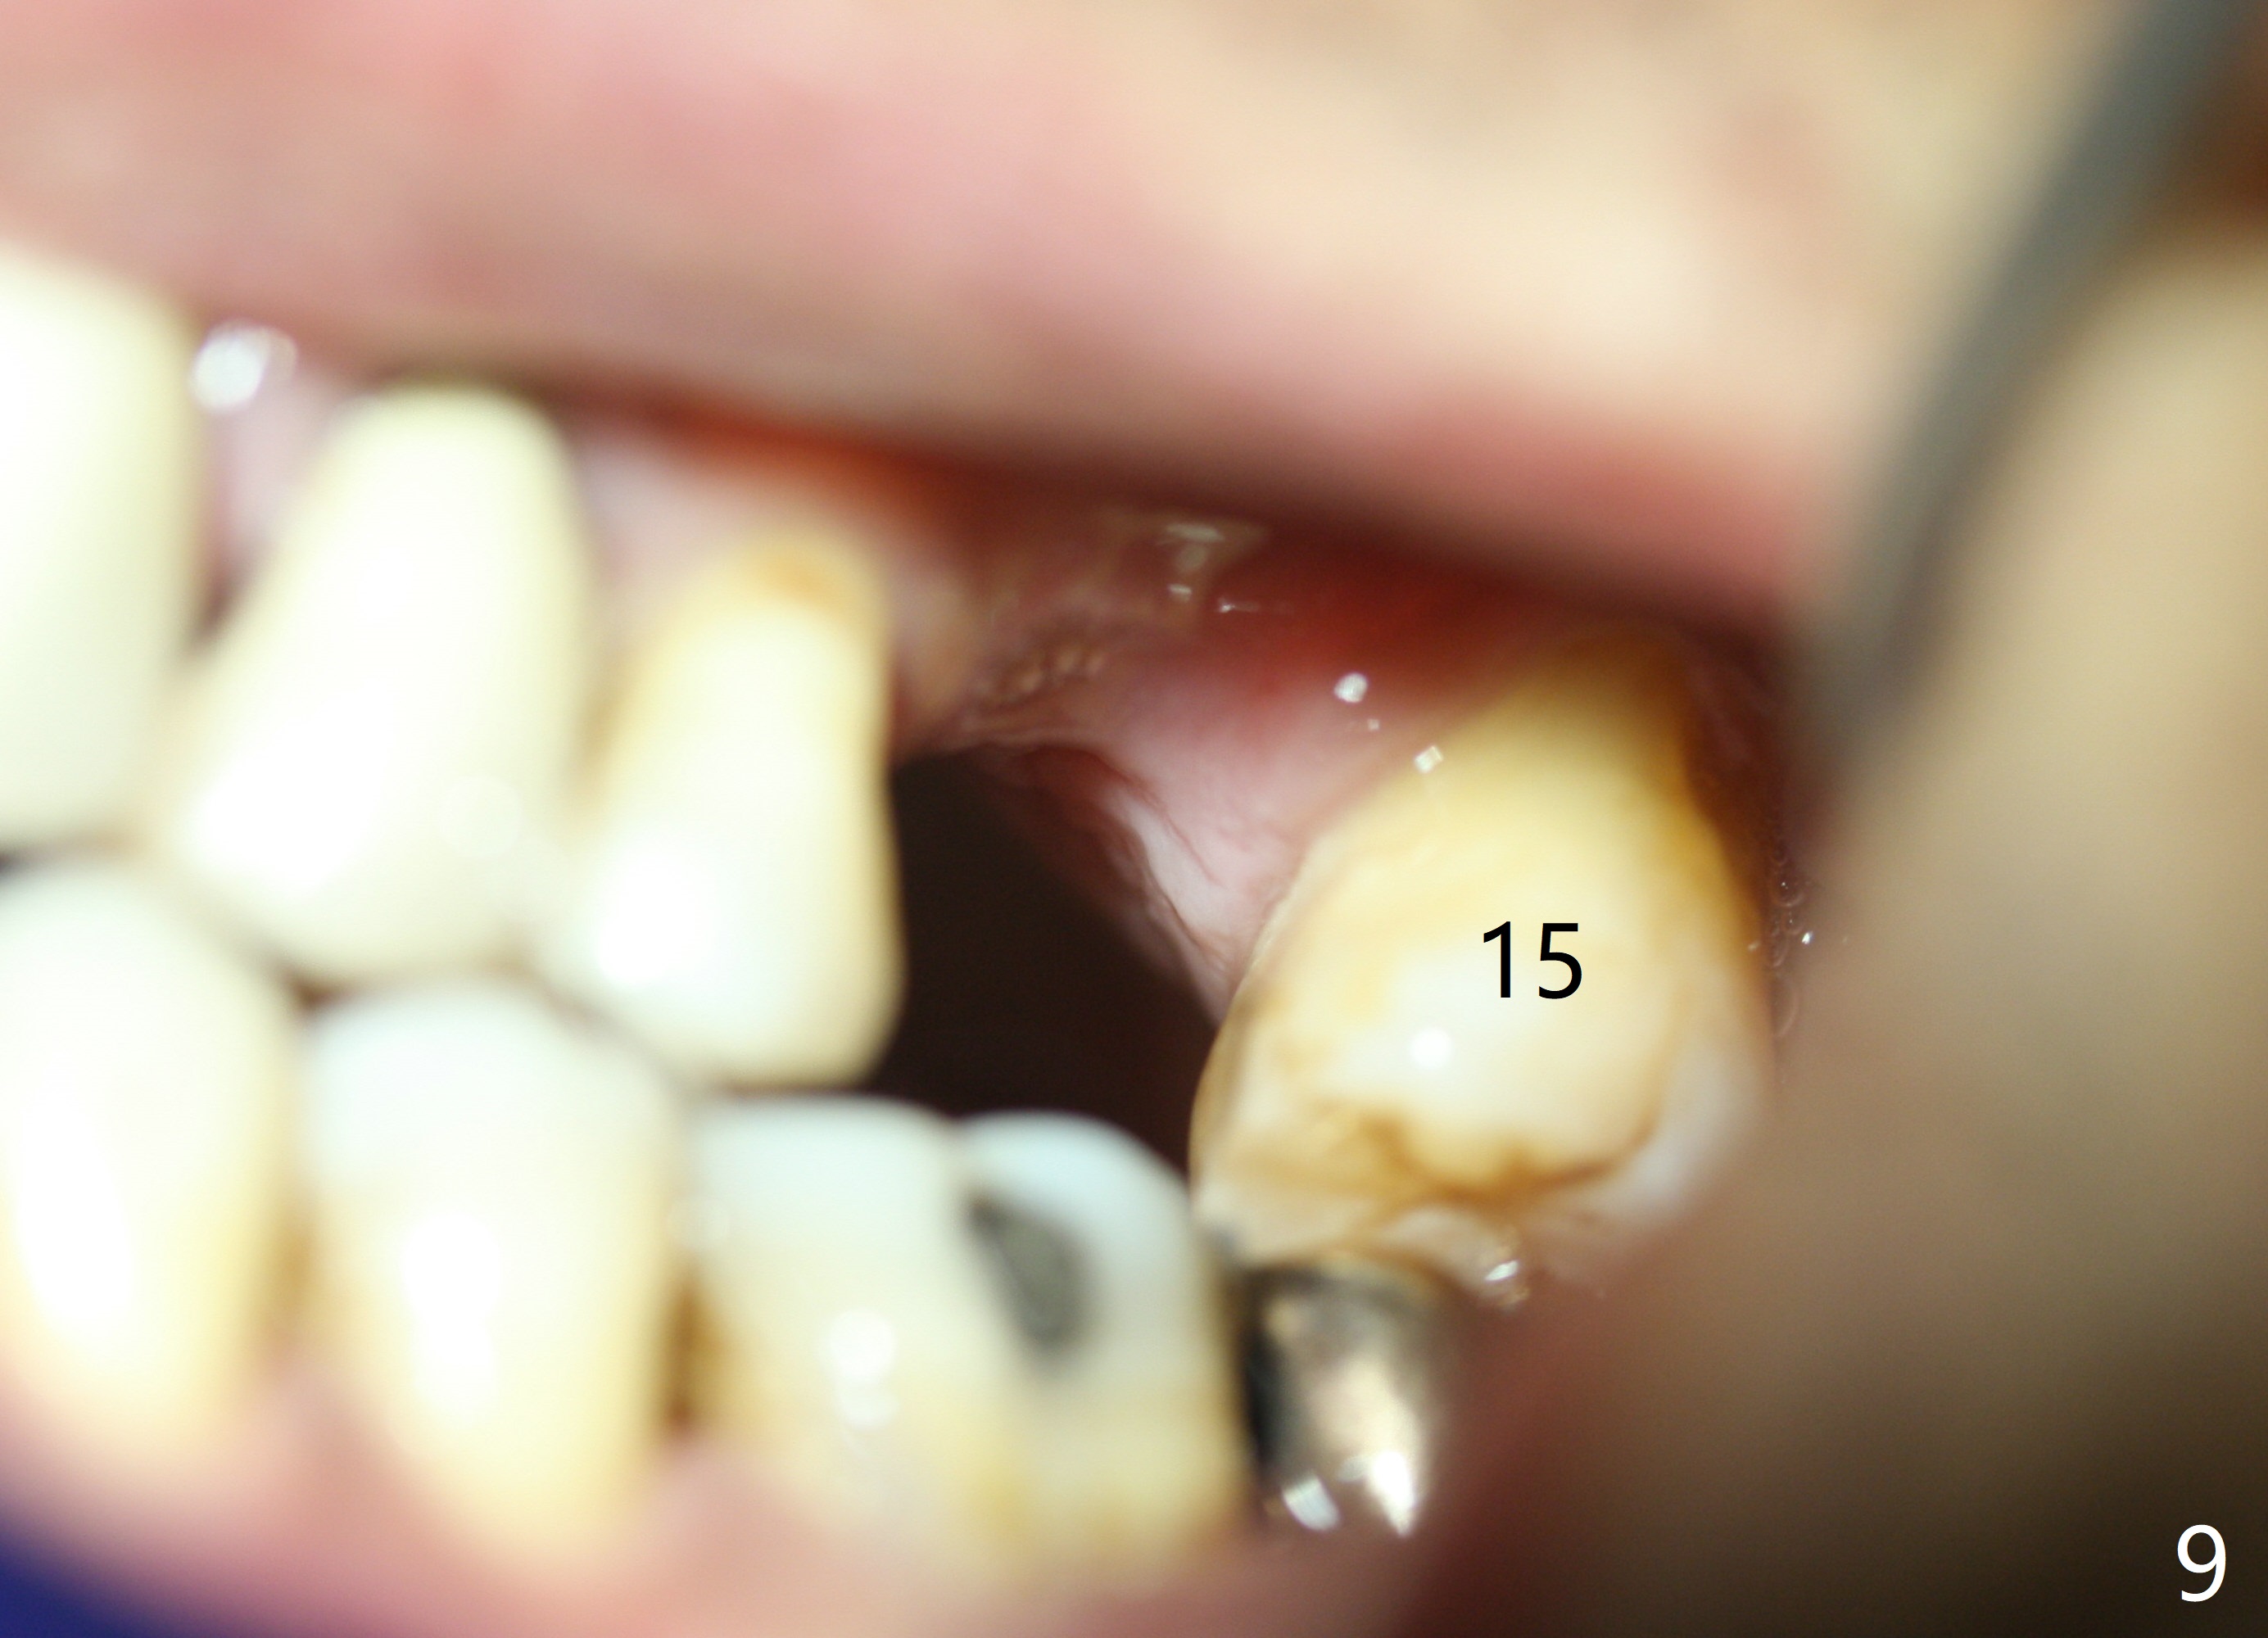

When the tooth #14 is extracted, the buccal plate is lost, while the apex of the palatal socket is perforated.  The palatal slope of the septum appears to be a suitable site for osteotomy, but the depth seems to be 2 mm.  After sequential osteotomy until 5.3 mm with drills, a 5.9 mm SM tap obtains stability (Fig.2).  A 5.9x8 mmm implant is placed with barely sufficient stability after 1 piece of PRF membrane and VeraGraft (Fig.2-4).  The implant rotates and dislodges when an abutment is being placed.  Neither do 6-8x17 mm Tatum taps achieve primary stability.  Socket preservation is performed, followed by periodontal dressing (Fig.5).  Primary stability might have been obtained if a smaller IBS implant with fins were placed in the palatal socket.  The periodontal dressing has dislodged 1 week postop; the socket appears healing (Fig.6,7).  Bone graft seems to be minimal or bone density of the graft is low (Fig.8).  The socket heals with a wide ridge 2 months post socket preservation, but the tooth #15 seems to be buccal (Fig.9) and mesial (Fig.10) shift.  After use of Magic Split and Expanders (until 3.8 mm for 13 mm), try 5 mm dummy implant (Fig.11).  If 6 mm one fails to achieve stability substantially, switch to 7 mm Tatum tapered tap provided there is enough mesiodistal space (use 8 mm implant positioner to gauze the space beforehand (preop)).  Consider using Vanilla (not Vera) Graft to fill in the gap between implant and osteotomy.  When primary stability is obtained, place a nonfunctional provisional to prevent further shifting (Fig.11 white outline).  After osteointegration, use the provisional (reline and separator) to distalize the tooth #15.